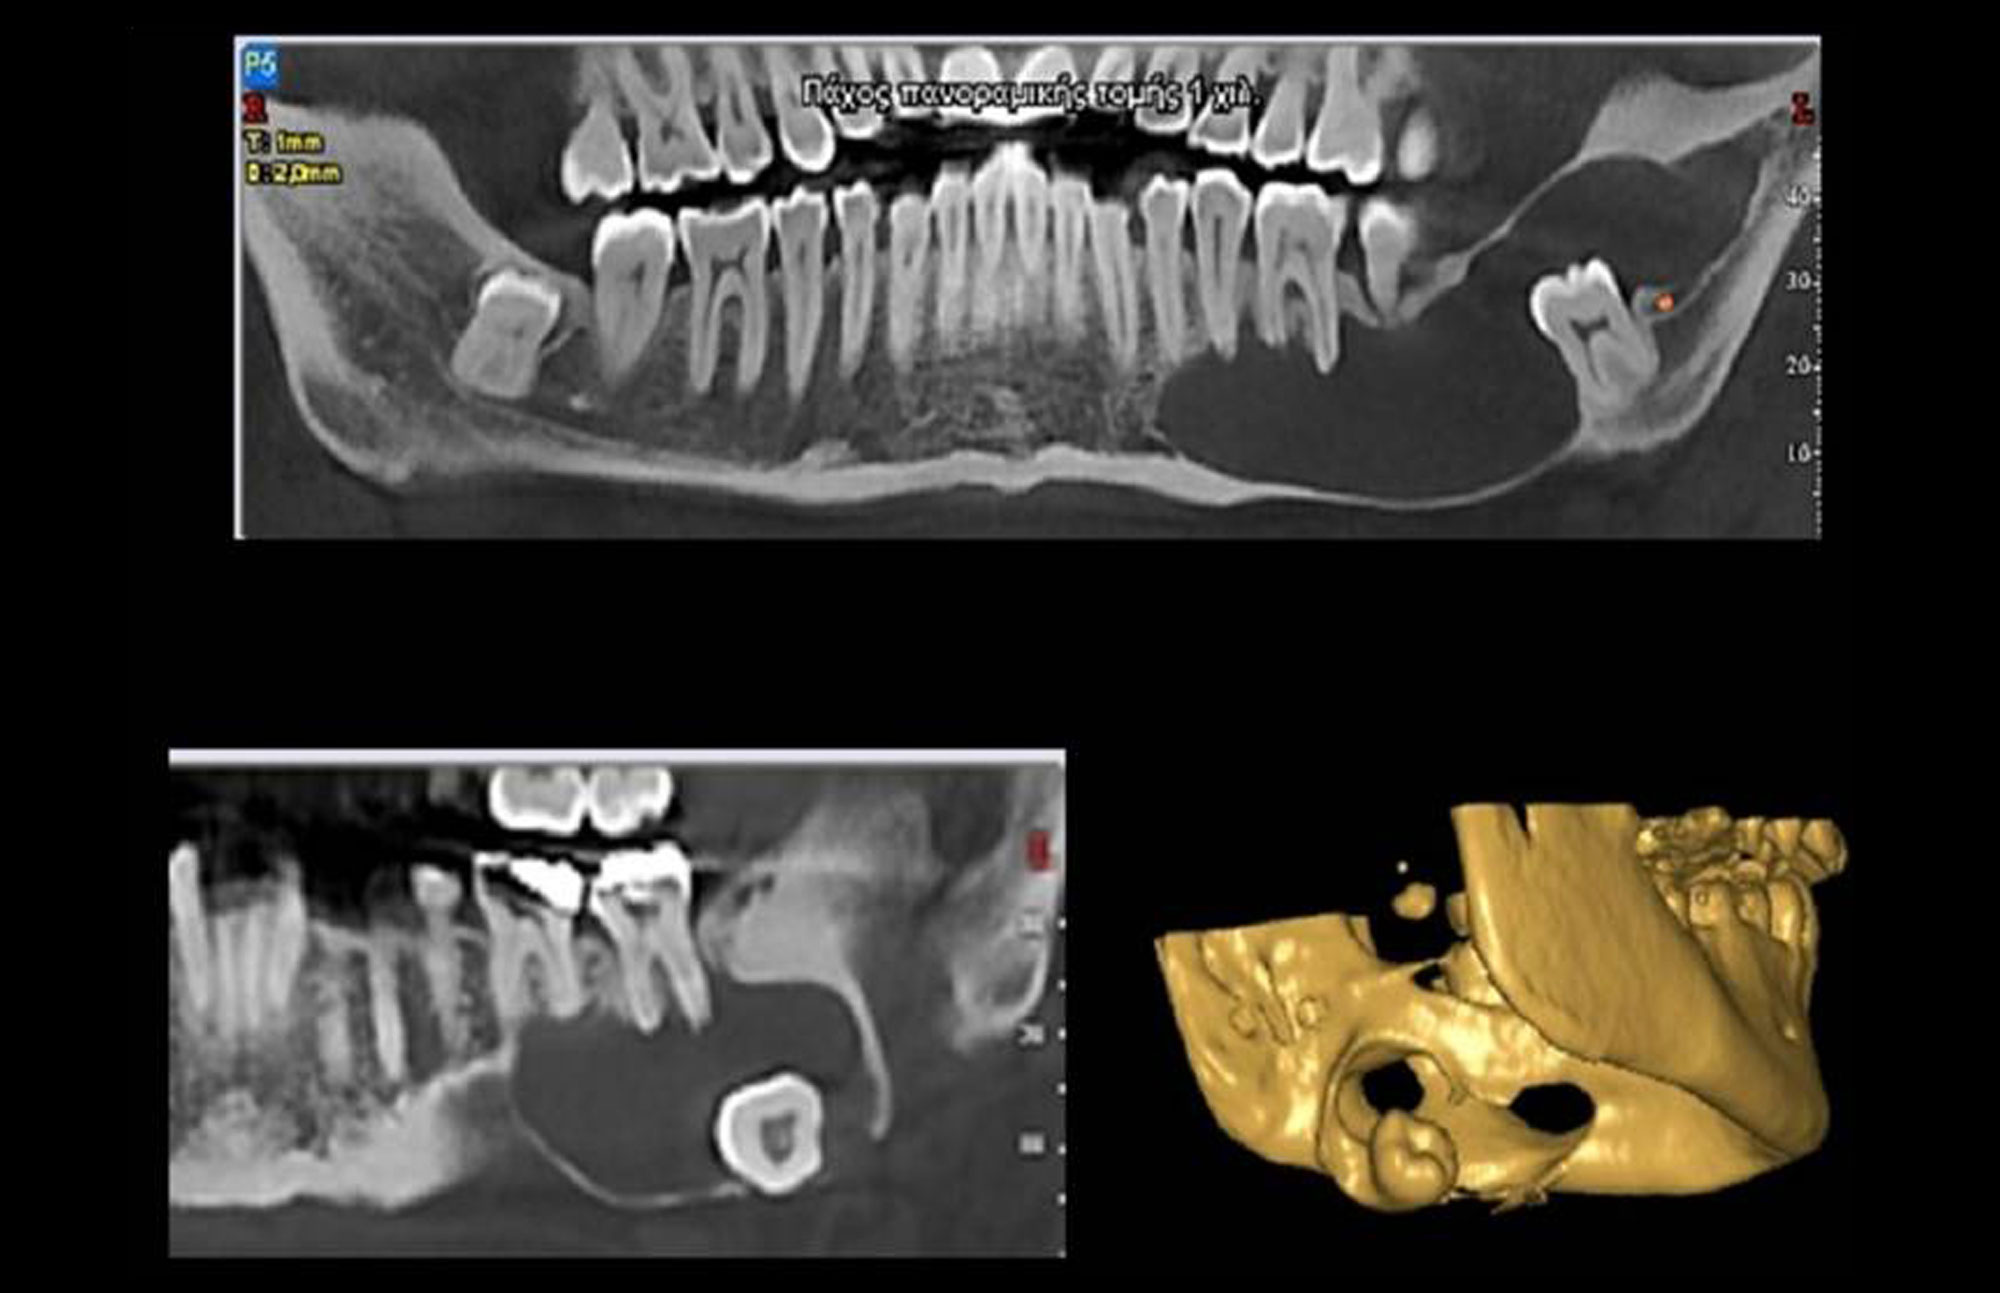

Για τη Διαφορική Διάγνωση, οι βλάβες των γνάθων ταξινομούνται σε μεγάλες ομάδες ανάλογα με την ακτινογραφική τους εικόνα (π.χ. Περιακρορριζικές Διαυγάσεις).